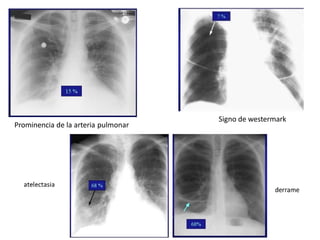

Prominencia de la arteria pulmonar

Signo de westermark

Prominencia de laarteria pulmonar Signo de westermark